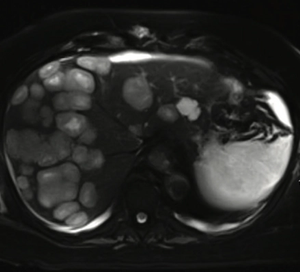

Ghulam Gous, MD, and colleagues report a case of glioblastoma with extensive liver metastases along with a review of previous reports of liver metastasis from glioblastomas and the possible mechanisms of metastasis.